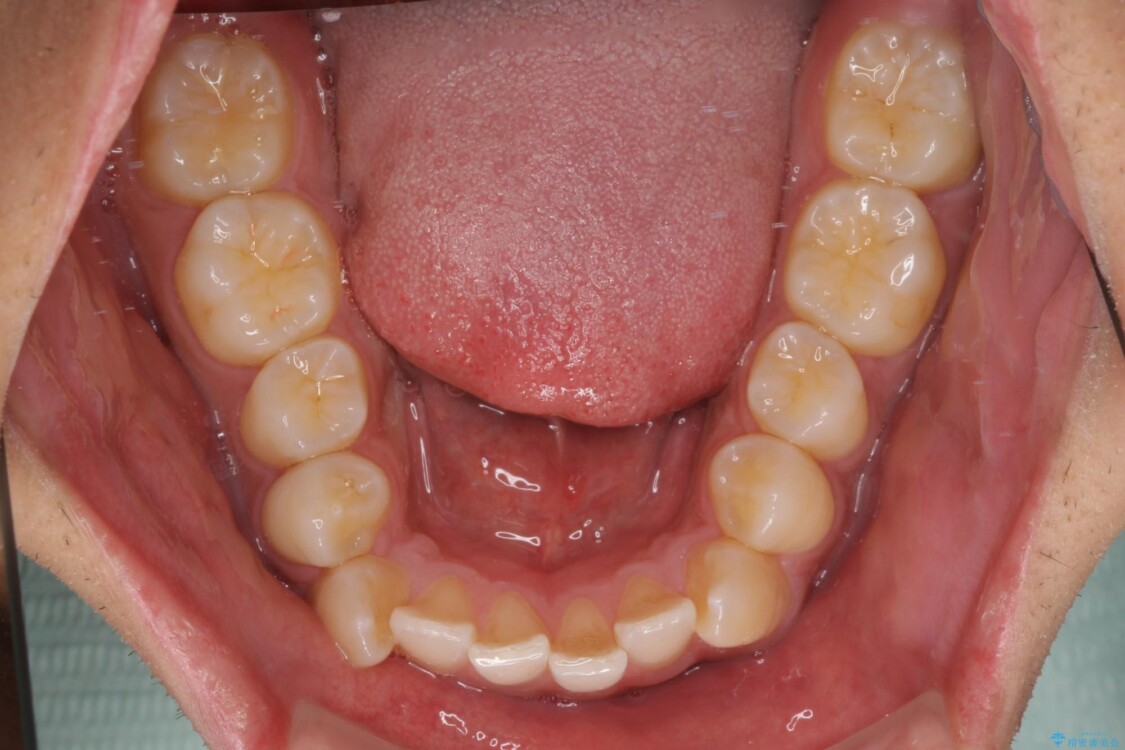

治療前

• 八重歯と前歯のガタガタを抜歯矯正で治療|クリアブラケット使用例 治療前画像

上下の前歯部に強い叢生(ガタガタの歯並び)があり、そのまま歯を並べると出っ歯になってしまう可能性がありました。